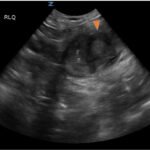

Small bowel diverticulitis is an uncommon subset of acute diverticulitis and can mimic many other intra-abdominal processes. As a result, imaging modalities such as ultrasound and computed tomography (CT) scan are especially important for timely recognition of diverticulitis and can expedite diagnosis and treatment and reduce complications. In the case described in this report, an 81-year-old male with history of esophageal cancer and recurrent diverticulitis with history of multiple bowel resections presented to the emergency department (ED) with right lower quadrant abdominal pain and constipation. Findings on ultrasound were suggestive of diverticulitis, and findings on CT of the abdomen and pelvis showed ileitis with phlegmon and micro-abscess suspicious for small bowel diverticulitis. ED providers should familiarize themselves with ultrasound findings of diverticulitis and be aware that diverticulitis can also present in the small bowel. Treatment of small bowel diverticulitis is similar to colonic diverticulitis.